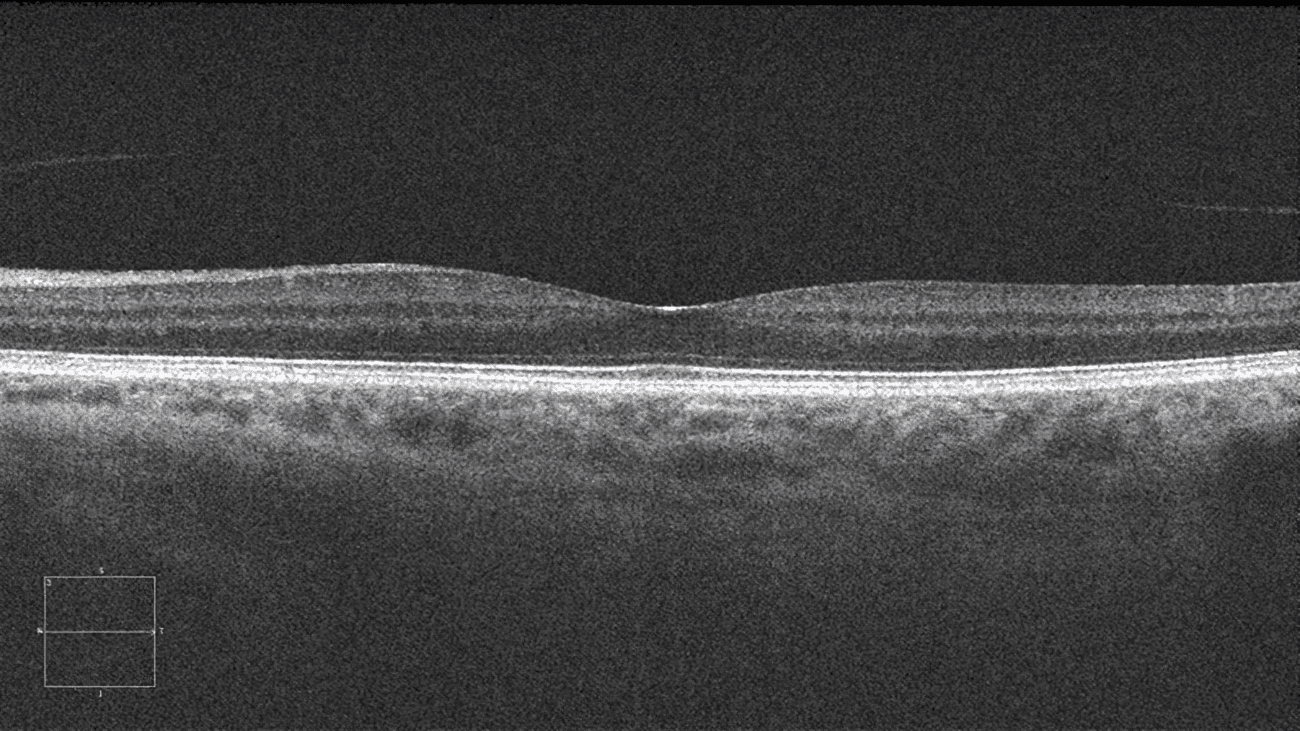

Investigar distintos métodos para realizar de manera adecuada el fine-tuning de modelos fundacionales de imagen a tareas específicas (prediagnóstico de cáncer de próstata, diagnóstico de patologías respiratorias y enfermedades oftalmológicas) y en su explicabilidad para ofrecer una mayor confianza al clínico.